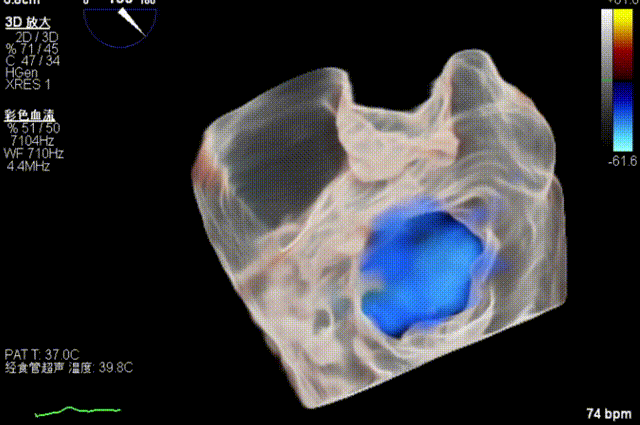

全麻后,二尖瓣夹合器系统在心前区的肋间切开3-4CM小切口,暴露心脏的心尖位置,送系统送入左心房,顺利到达病变二尖瓣区域。在经食道超声辅助下,术者通过反复评估二尖瓣反流位置、抓捕位置、反流程度,首先在2偏3区位置处于二尖瓣闭合线垂直进行巧妙夹合。在2区靠近3区位置处植入了1枚ValveClamp®MVC-IIf夹,最终评估评估反流降至轻度,平均跨瓣压差降至2mmHg,手术取得圆满成功。

术中超声(关键步骤)

最终在A3P2位置夹合,前叶夹合量10mm,后叶夹合量8mm,剩余瓣口面积3.45cm²,平均跨瓣压差2mmHg,反流基本消除。